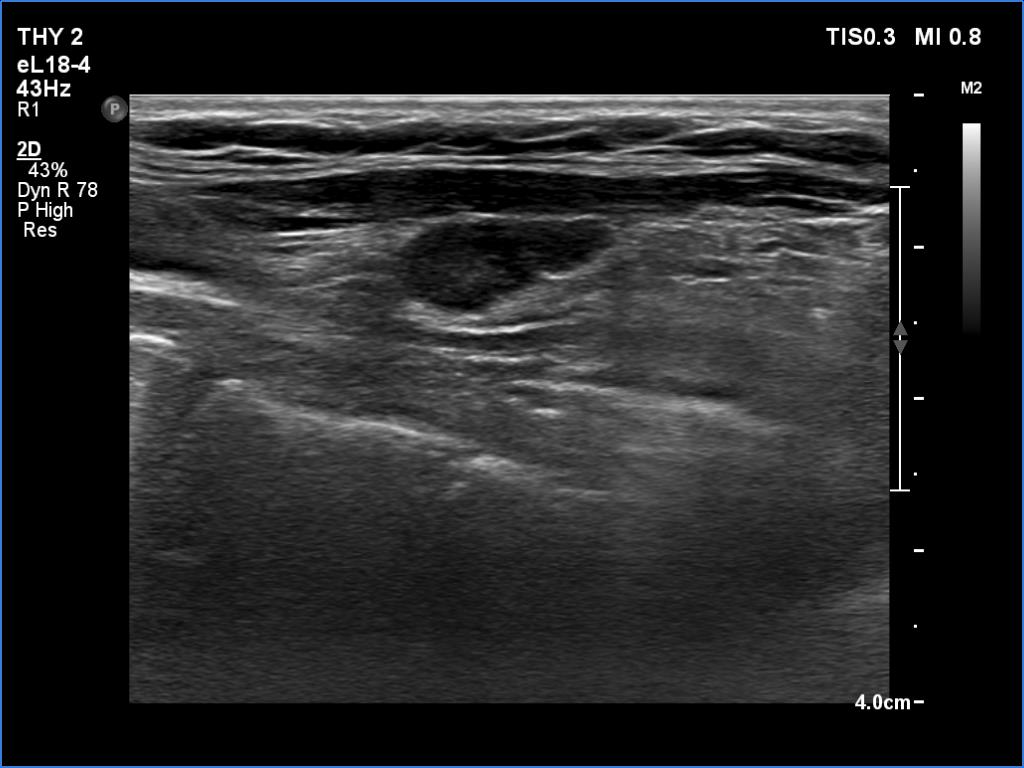

Introduction - case 162 (ultrasonographic picture 6)

Left lobe, longitudinal scan - with less harmonic settings. Regarding the presence of cystic content, this is the only relevant image. The less harmonic settings can reveal the real situation, i.e. the ventral part of the node is solid. Moreover, in contrast with transverse scan, the probe could be correctly placed to the neck of the patient.